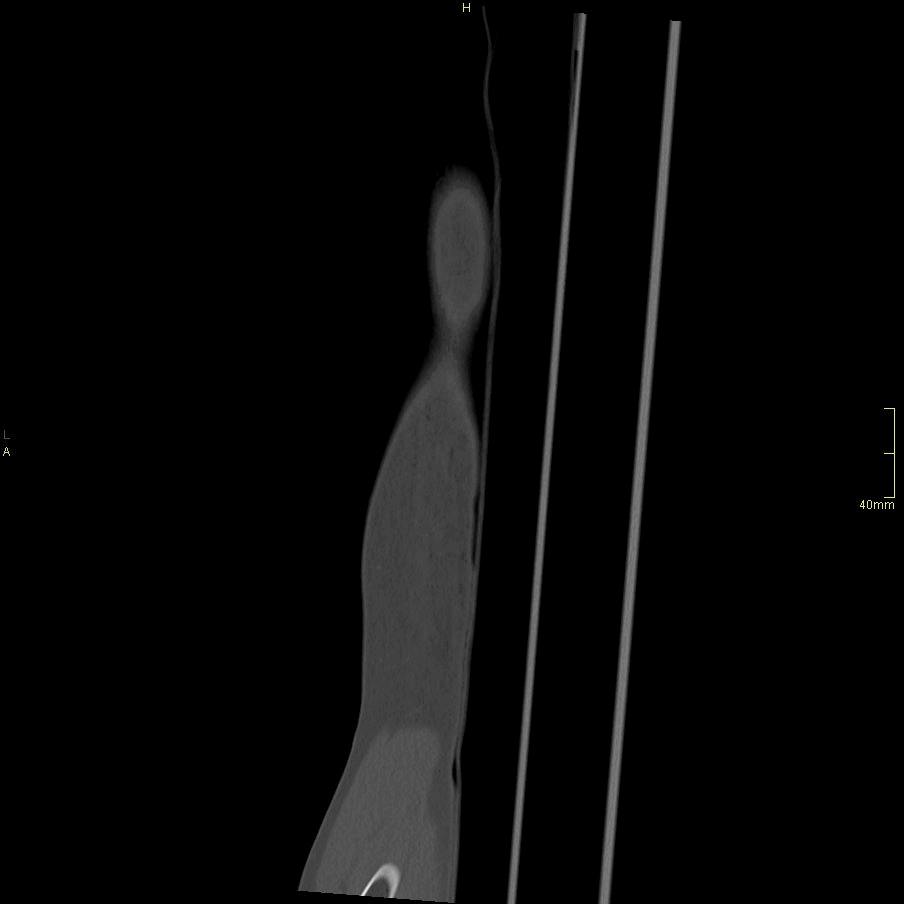

CT Humerus Contrast- Soft tissue window (axial)

CT Humerus Contrast- Soft tissue window (coronal)

CT Humerus Non Contrast- Soft tissue window (axial)